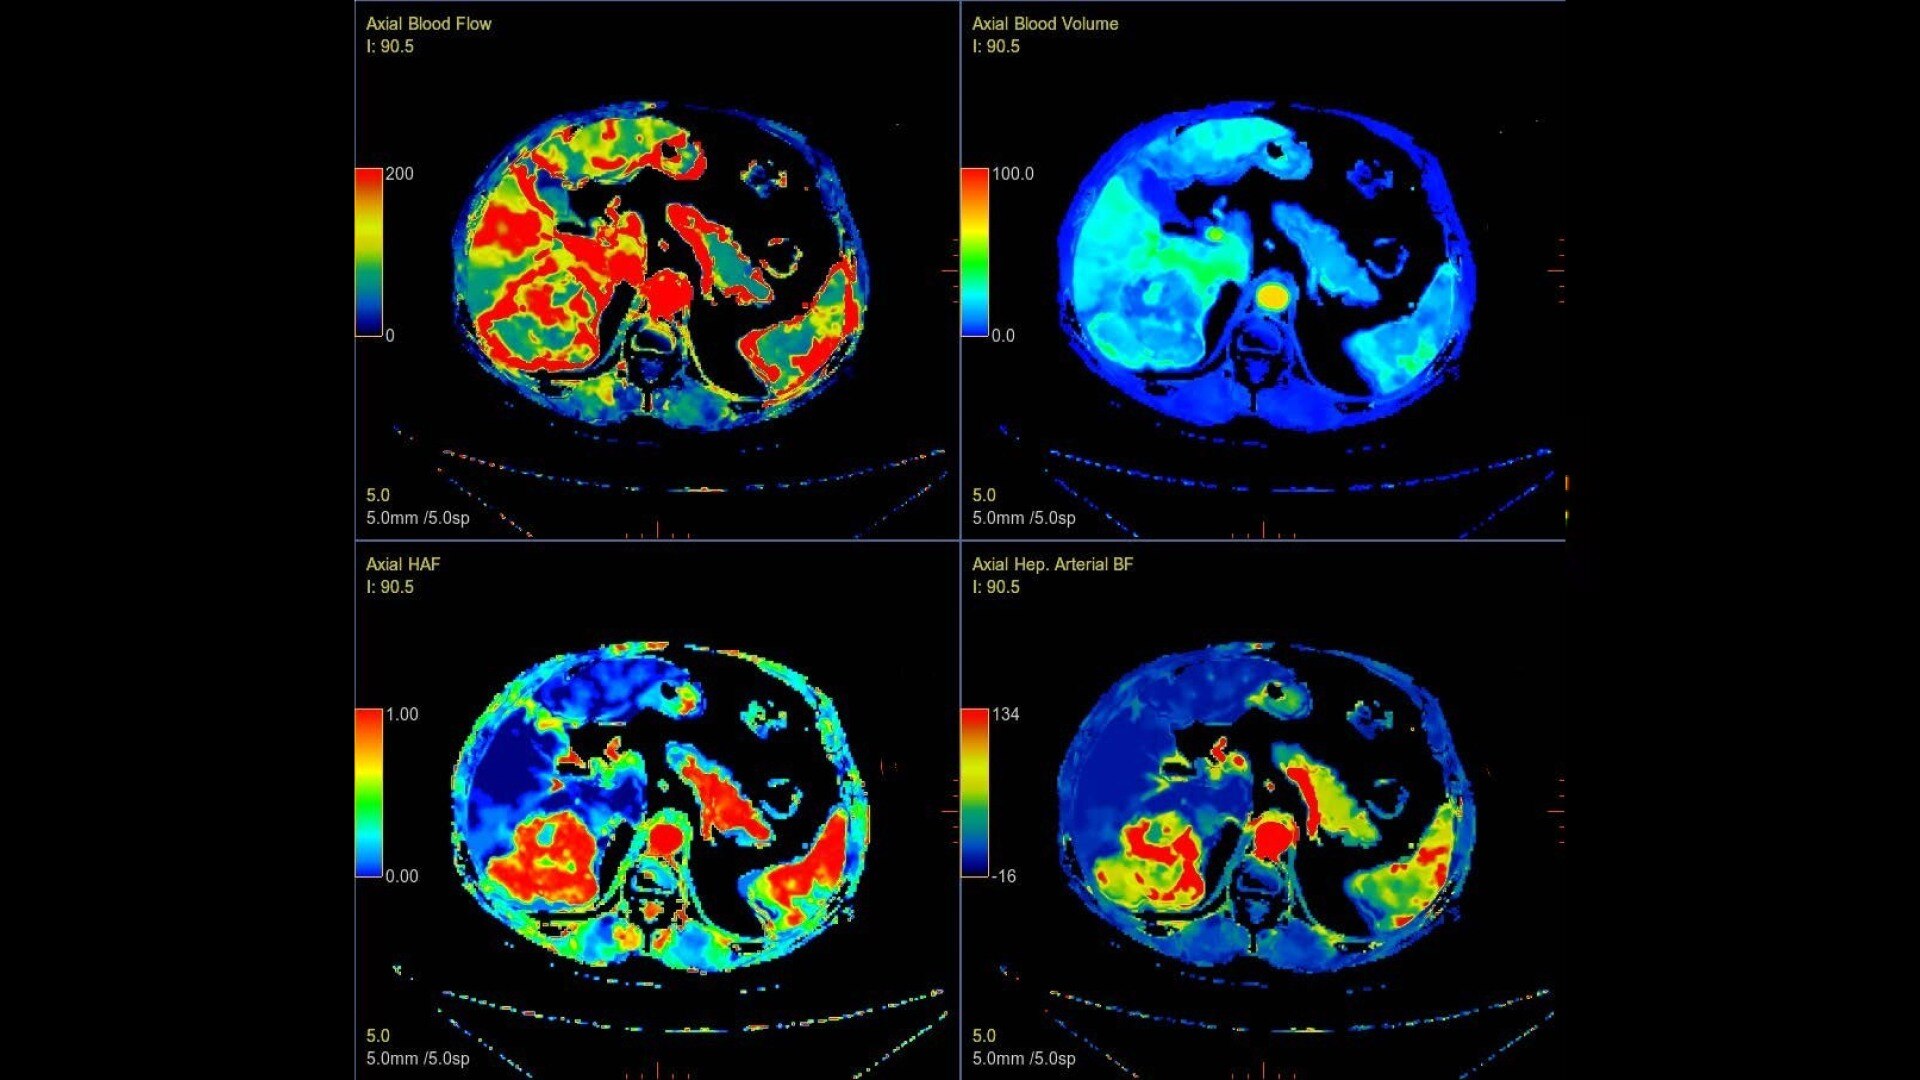

Body perfusion

Optimized protocols for kidney, soft tissue, liver perfusion and other body tumors

CT Body Tumor Protocol

• Automatically produces functional maps once the user selects an artery using a simple and intuitive workflow

• Leverages most of the advanced algorithm settings that are part of the Brain Stroke protocol

• Optimized protocols for pancreas, prostate, kidney, soft tissue, spleen, bone and liver perfusion

• CT Non-Rigid Registration: Fully automated protocols used for dynamic body acquisitions to register data for use in perfusion analysis

CTPerfusionfeatureheroimage-2